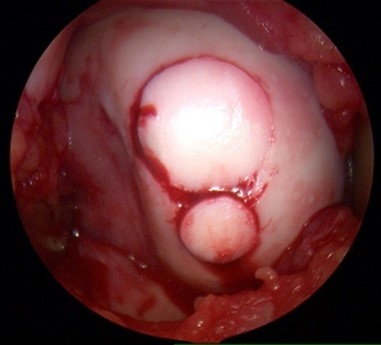

OATS Implantation with Snowman Technique

Arthroscopic View of Large Trochlear Chondral Lesion